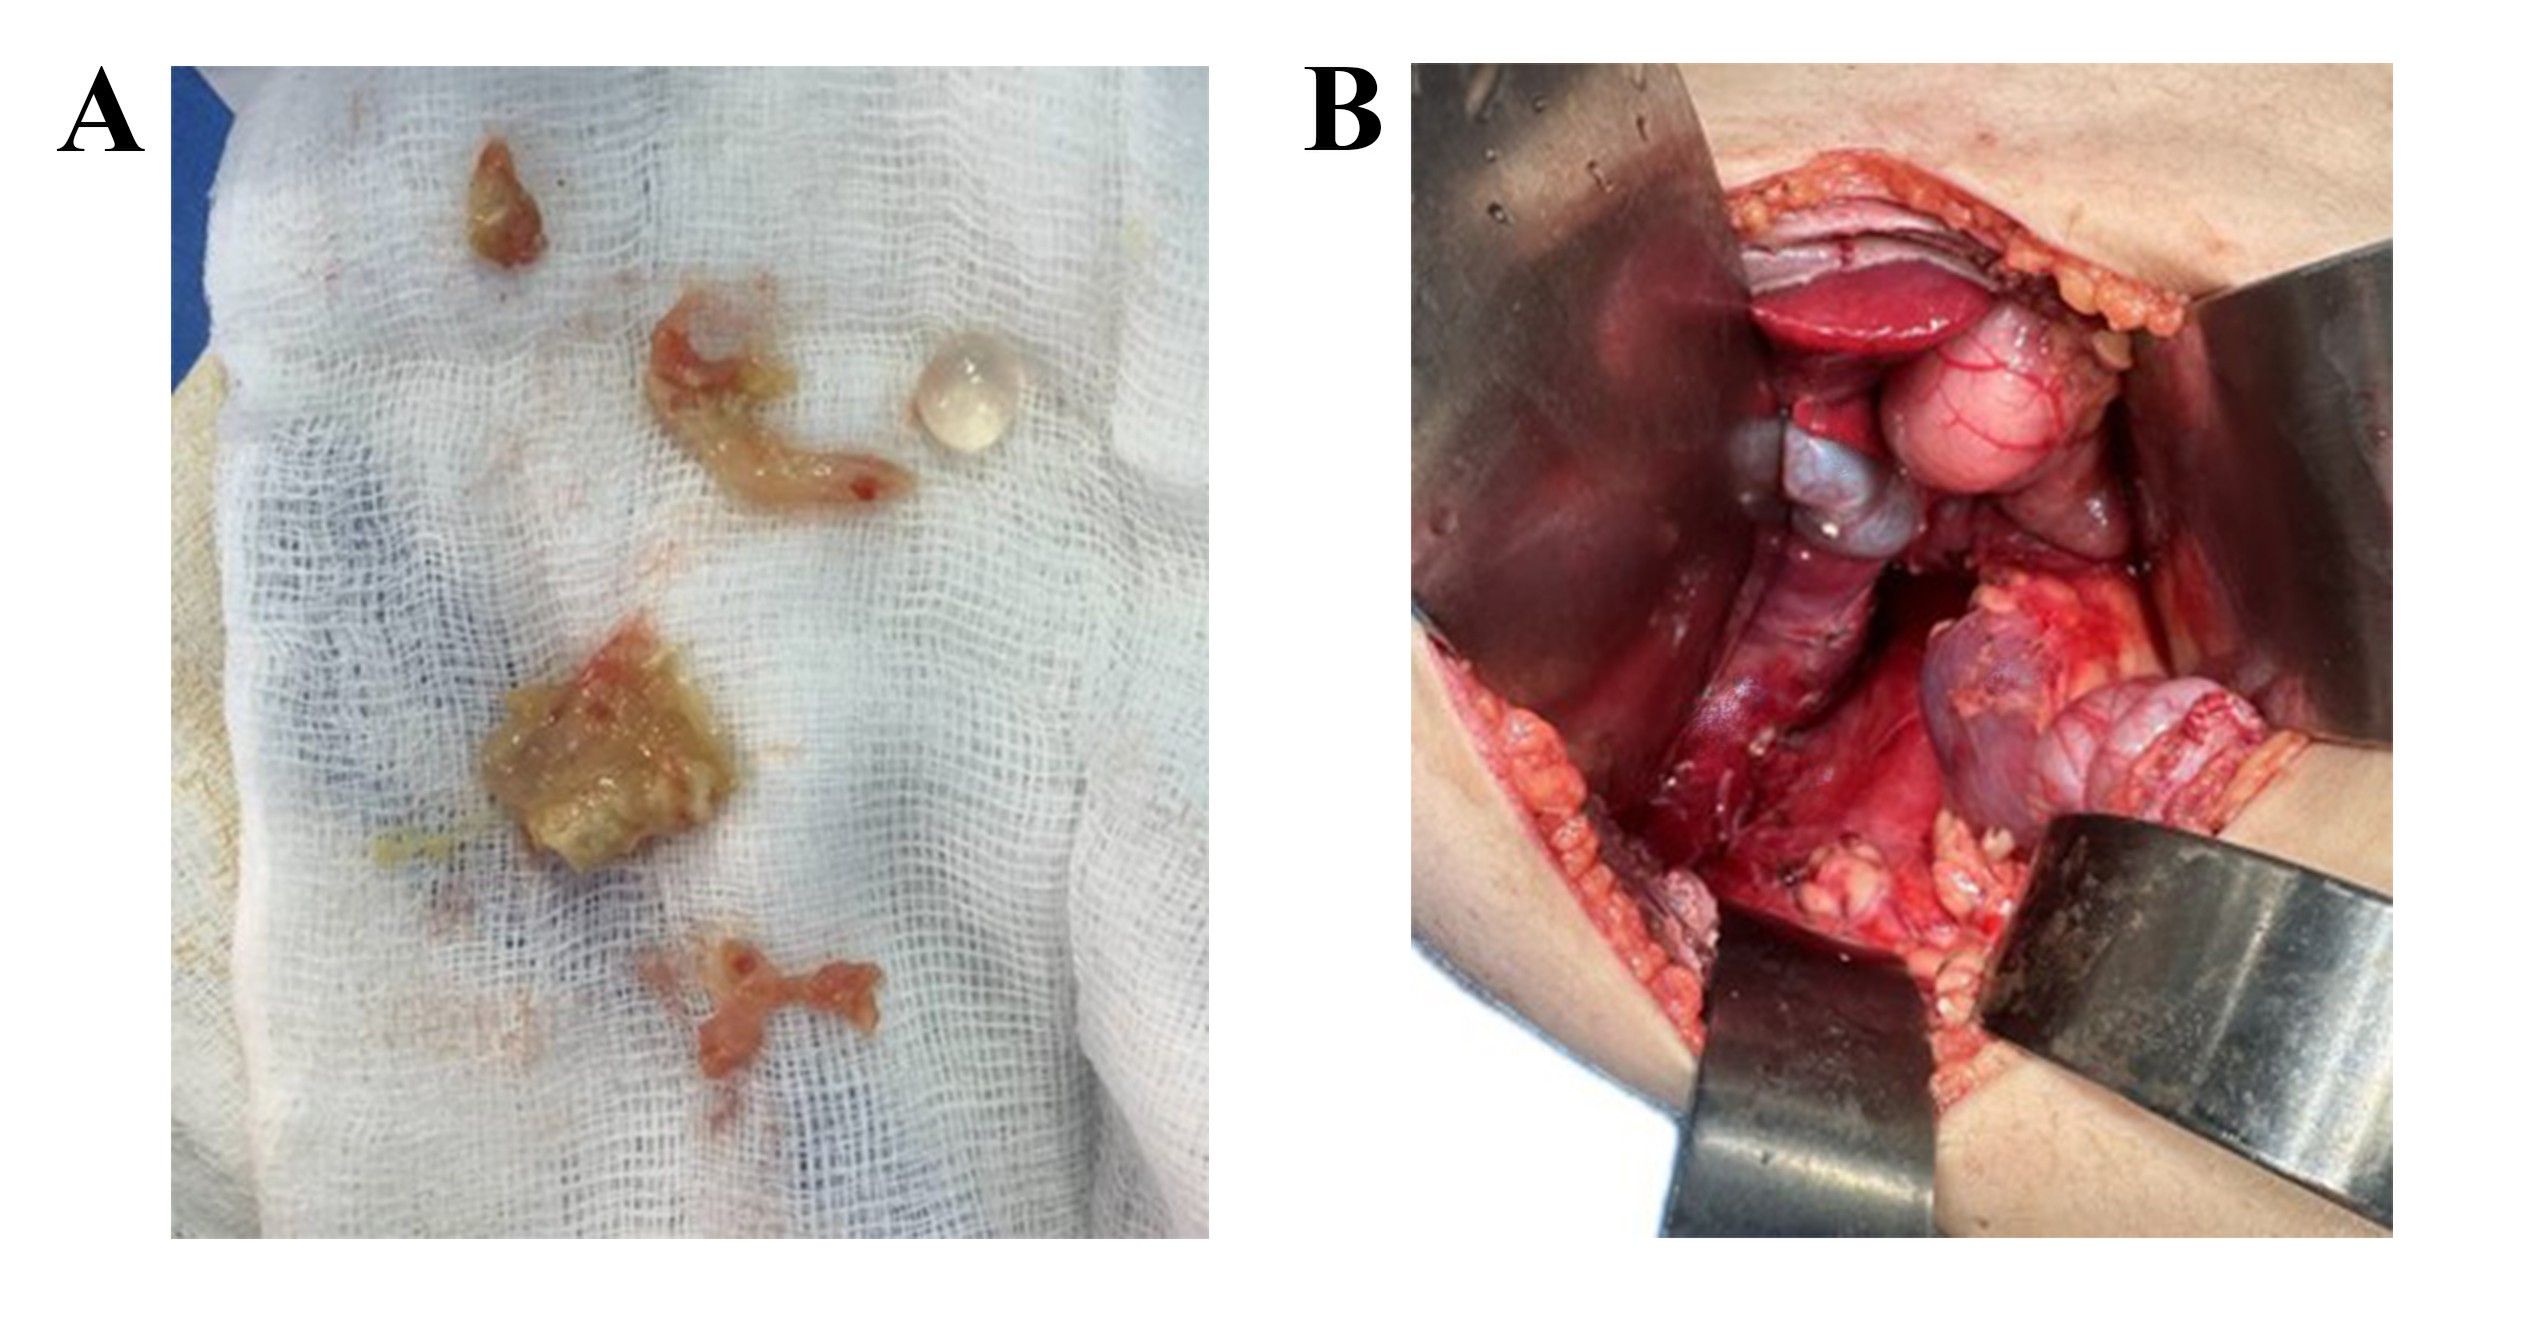

All patients underwent surgery under general anesthesia and were positioned supine with the neck extended and elevated using a roller placed beneath the shoulders. If visible, a 4 cm transverse collar incision was made in a natural skin crease of the lower neck for cosmetic purposes. Subplatysmal flaps were elevated superiorly and inferiorly to allow adequate thyroid gland exposure. A circular skin flap was then raised, with dissection carried laterally, medially, and toward the upper and lower cervical regions.

The midline between the strap muscles was divided, and the muscles were retracted laterally to expose the thyroid gland. Dissection commenced with ligation of the middle thyroid vein, followed by the superior and inferior pedicles. The superior and inferior thyroid vessels were ligated and divided close to the thyroid capsule to preserve the recurrent laryngeal nerves and avoid compromising the parathyroid gland vasculature. To minimize thermal injury, electrocautery use was limited; instead, multiple suture ligatures were applied to control oozing. Both sharp and blunt dissection techniques were employed to identify and preserve the recurrent laryngeal nerves, with all dissections maintained close to the thyroid capsule. The parathyroid glands were preserved in all cases, and surrounding adipose tissue was retained to maintain vascular integrity. In cases where devascularization was suspected, parathyroid autotransplantation into the sternocleidomastoid muscle was performed.

Of the 11 patients, 7 underwent total thyroidectomy. One of these patients underwent additional lateral and central neck dissection, with identification and preservation of the internal jugular vein, spinal accessory nerve, and phrenic nerve. The remaining 4 patients underwent lobectomy, performed using the same surgical technique but limited to the involved thyroid lobe.

After each procedure, hemostasis was confirmed. Closed suction drains (RediVac®) were placed in the patients. The strap muscles were reapproximated in the midline, and the skin was closed with absorbable subcuticular sutures and Steri-Strips. All patients tolerated the procedure without intraoperative complications.

On gross examination, HTT typically presents as a solid, well-circumscribed mass, or less commonly, as an encapsulated tumor, with colors ranging from yellow to tan, opposite to PTC, which is usually white and does not have a capsule. HTT generally lacks invasion into the capsule, vasculature, or thyroid parenchyma [5,7]. However, Gowrishankar reported a case in which invasion and malignant behavior were observed in HTT [13].